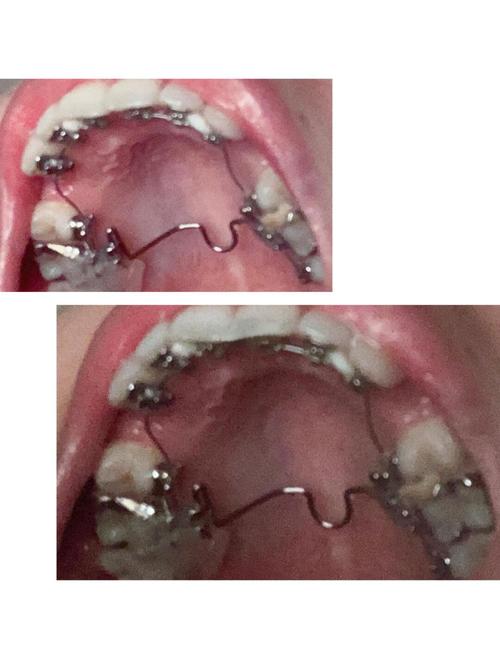

- 个性化定制: 每一颗牙齿的舌侧托槽都是根据患者牙齿的精确三维模型,通过计算机辅助设计和制造技术(CAD/CAM)个性化定制的,托槽的底座与牙齿舌侧表面完美贴合,弓丝也是根据牙齿移动路径精确弯制的。

- 个性化托槽与弓丝制造: 利用CAD/CAM技术,根据设计方案为每颗牙齿定制舌侧托槽,并制造一系列用于不同矫治阶段的个性化弓丝。

- 间接粘接: 这是最关键的技术之一,医生在模型上预先将所有托槽精确粘接到牙齿舌面的理想位置,然后制作一个转移托盘,复诊时,利用转移托盘将托槽一次性、精确地转移到患者口内,大大提高了粘接效率和准确性,减少了椅旁操作时间。